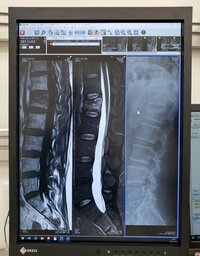

そして、同日になって知り合いの整形外科に足を運んだところ「MRI と レントゲンを撮ってもらった結果」「第1腰椎 圧迫骨折, 全治2ヶ月」「肘は~関節内骨折, 全治6週間」とレントゲン写真とともに報告。「打撲どころか, 折れてんじゃん・・・」「そりゃ, 痛いはずだよなぁ・・・!」としみじみつづった。